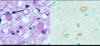

Name/grade of tumor

Name of protein that stains positive

MRI enhancing: Y/N?

Low grade astrocytoma

GFAP positive

Non enhancing

Anaplastic astrocytoma